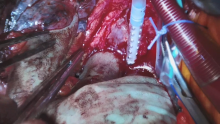

When Things Go Wrong in Thoracic Surgery: A Middle Lobectomy With Bleeding That Required Cardiopulmonary Bypass to Address [1]

This is a video showing a procedure performed by open thoracotomy with a head camera that records audio. The patient had a large middle lobe tumor and had an ICD, an impaired left ventricular function, and previous coronary artery bypass grafting. Unfortunately, the operating surgeon got into a bleeding scenario that required the whole team to work together to get out of this problem.

This is a 34 minute video where the viewer can hear exactly how it went. The team has taken away many learning tips from this case, as this was the first time that the operating surgeon had to use cardiopulmonary bypass to rescue a bleeding situation in thoracic surgery. With good control of the bleeding and good planning, the team and patient were fortunate to have a good outcome.